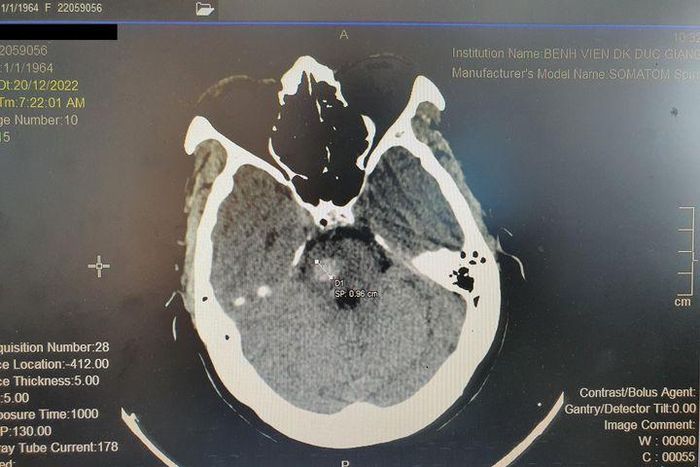

Bệnh nhân ngay lập tức được các bác sĩ đánh giá và chụp phim cắt lớp sọ não, chẩn đoán nhanh chóng được đưa ra là xuất huyết cầu não. Bệnh nhân T. ngay lập tức được chuyển đến đơn nguyên điều trị đột quỵ để tiến hành các can thiệp cần thiết.

Hình ảnh chụp phim não của bệnh nhân T. Ảnh BVCC